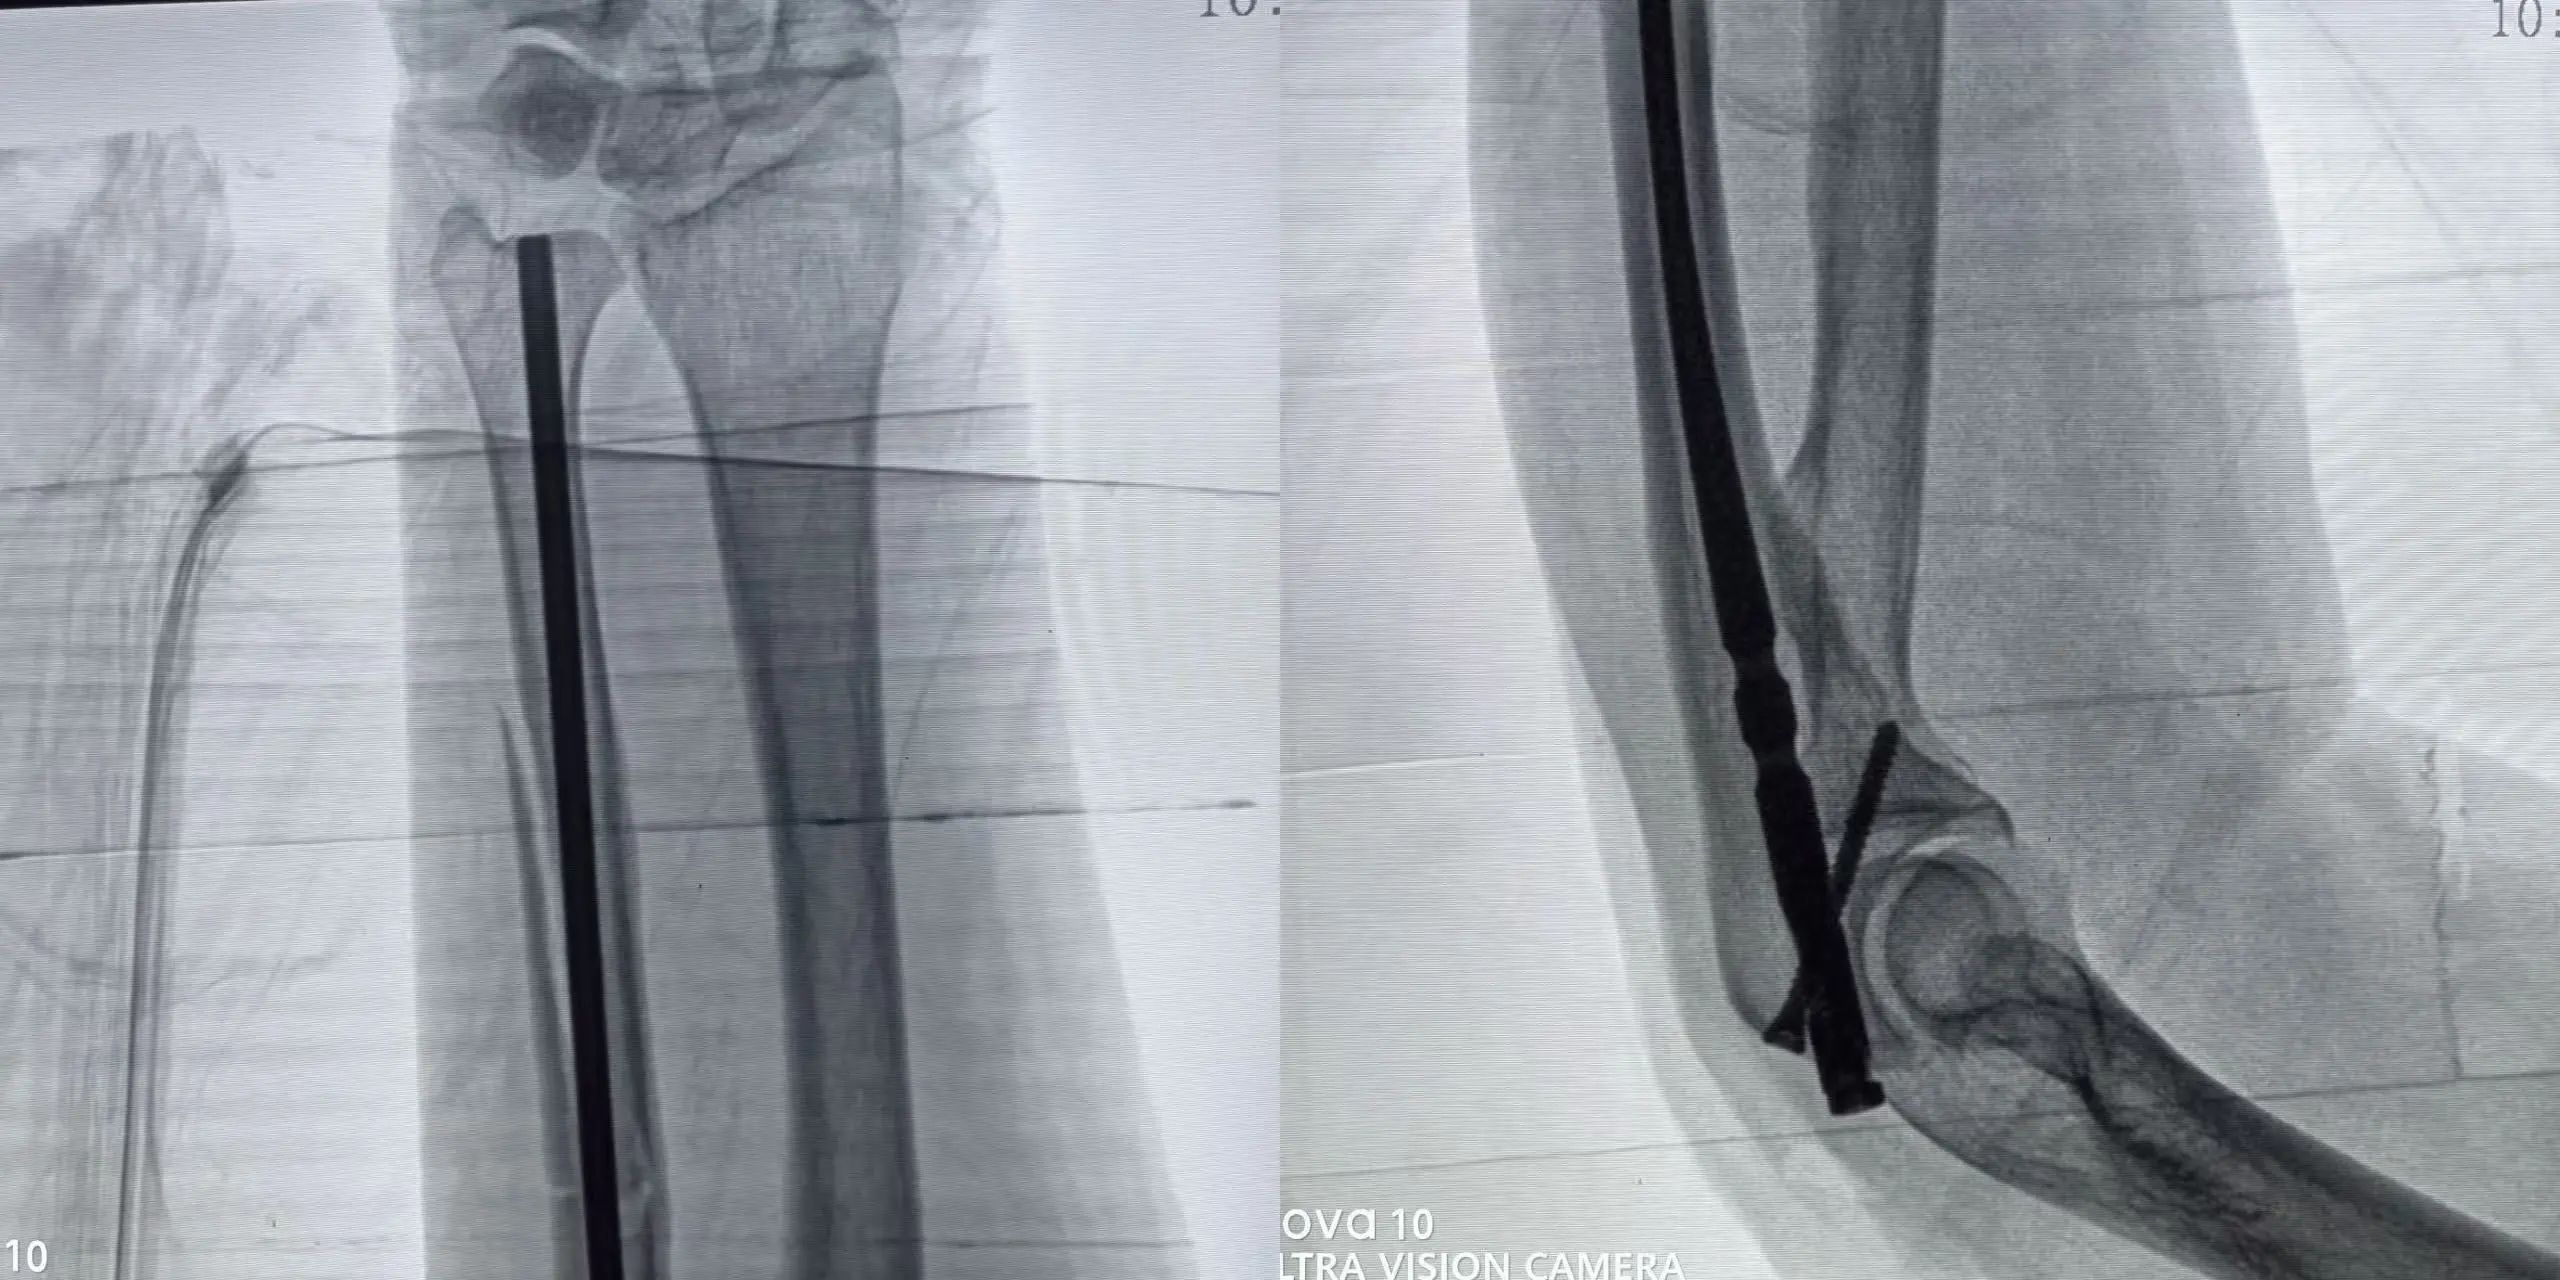

手术在孙杰院长的指导下,由骨三科团队默契配合,精准操作,仅通过几个小切口,便成功完成骨折复位和髓内钉固定。 手术创伤小、出血少、恢复快、疼痛轻,术后患者恢复良好,对手术效果非常满意。

术 后